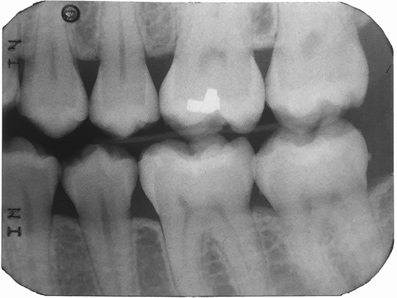

Fig 2.  Circumferential gumline decalcification (Fig 1) and bitewing (Fig 2) of a 28-year-old woman.

Figure 2

A 28-year-old woman, who previously had braces, had circumferential gumline decalcification (Figure 1) and wished to arrest lesions before they worsened (bitewing, Figure 2). The following protocol is consistent with the product instructions for the resin infiltration material from DMG America, which is the only commercially available resin infiltration system in the US.